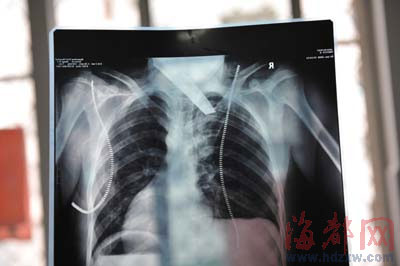

前晚,在第一醫(yī)院急救室,經(jīng)過4個多小時的搶救,醫(yī)生將匕首從小勇身上取出,發(fā)現(xiàn)這把匕首的刀尖扎斷了1厘米。由于小勇肺部被刺中,昨天上午,醫(yī)生再次進行了3個多小時的手術(shù),切除了受傷的部分肺,直到下午,小勇才挺過來!巴α艘灰,現(xiàn)在總算醒了過來。”楊女士一夜沒睡,守在手術(shù)室外7個多小時,生怕兒子再醒不過來。不過,由于傷勢嚴(yán)重,小勇目前戴著氧氣呼吸,仍未脫險。